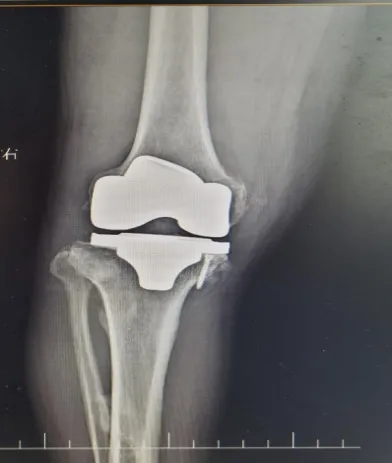

何爷爷在梓潼县人民医院骨科接受了人工全膝关节置换术,术后他的疼痛显著缓解,关节功能逐步恢复。术后当天在康复师的专业指导下,逐步开展膝关节功能锻炼,以促进血液循环和防止血栓形成。术后第2天,何爷爷便能在医护人员陪同指导下使用助行器下床活动。

经过科学有效的锻炼,仅仅2周后,何爷爷已能独立行走,日常活动能力大幅提升,膝关节疼痛显著缓解,不再需要依赖止痛药物。何爷爷对手术效果非常满意,并对骨科团队的医疗水平和护理服务给予了高度评价。